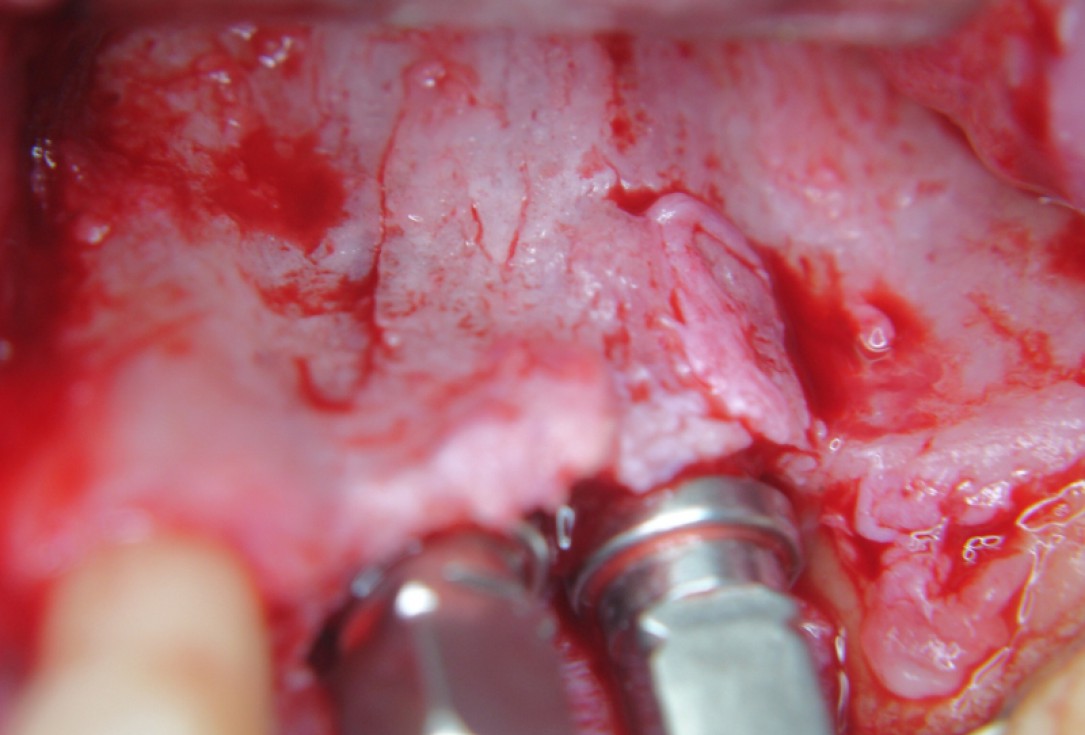

Three implants placed in a narrow posterior mandible